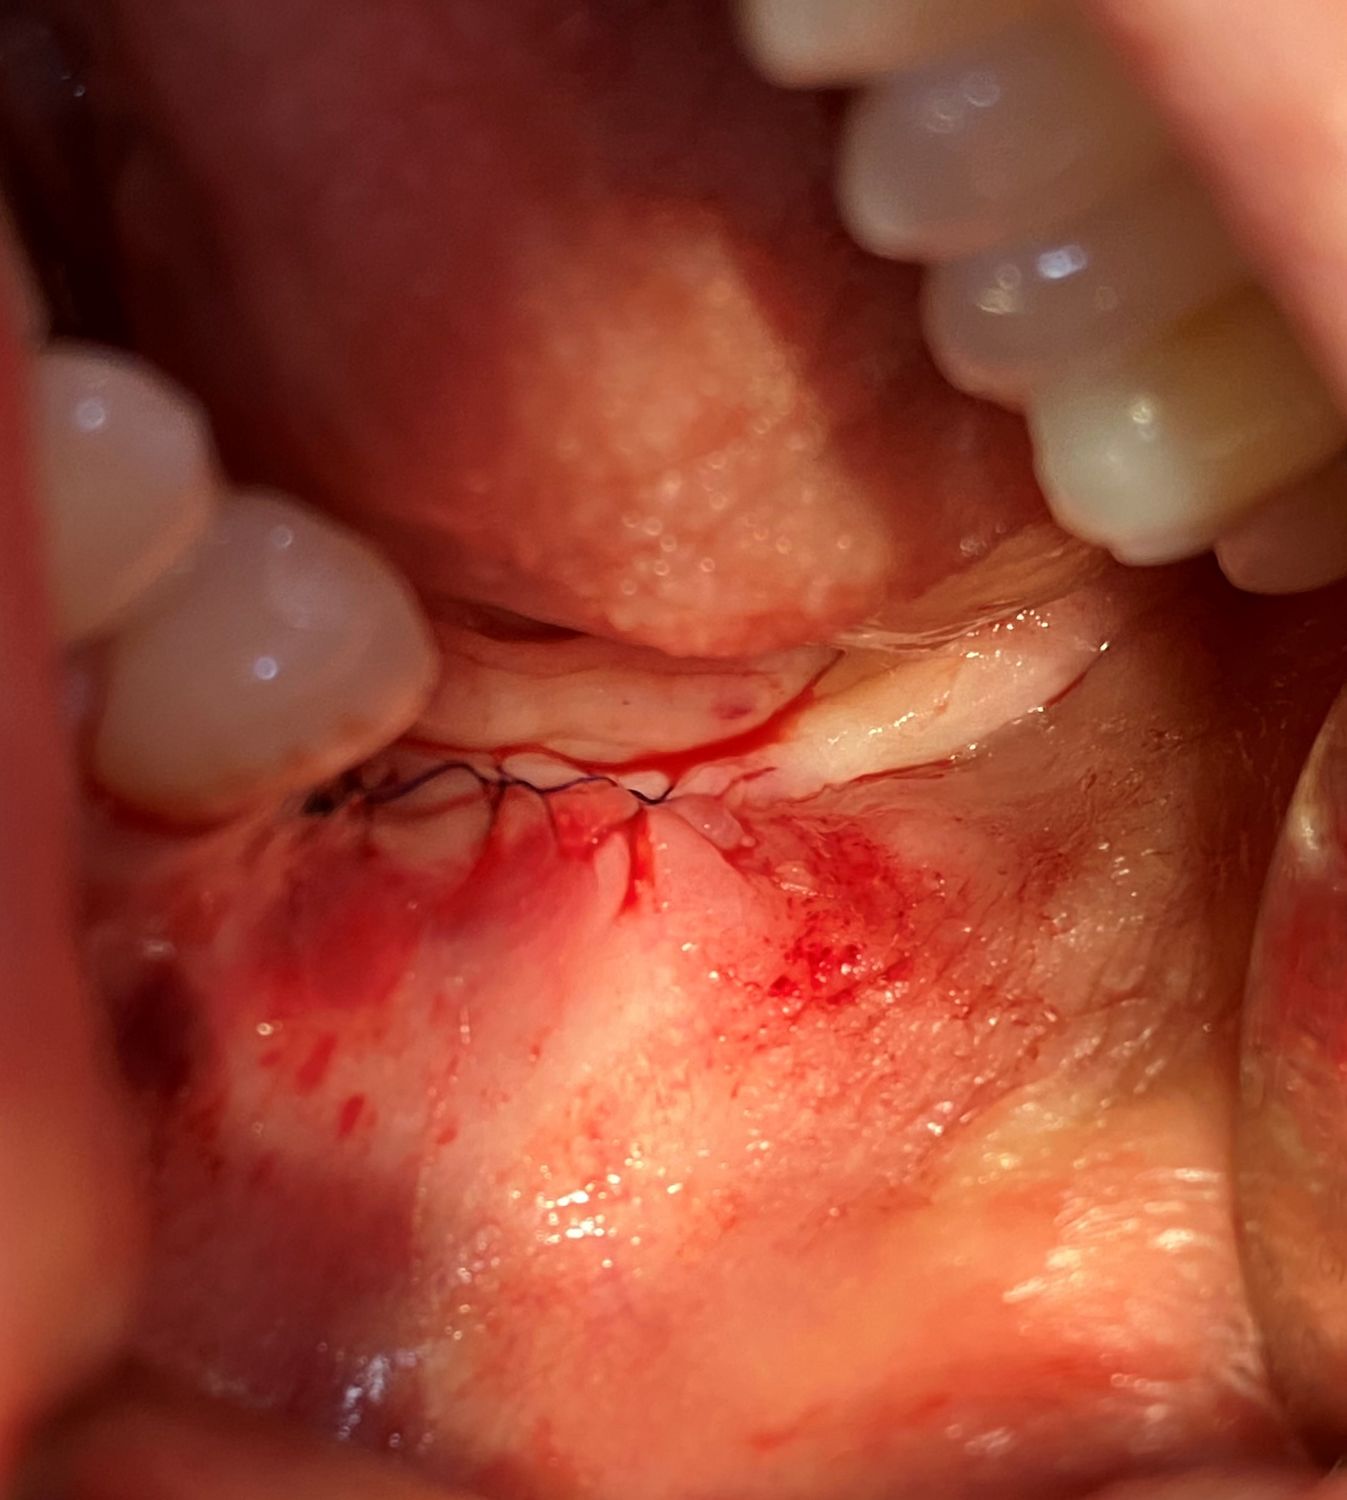

Пациент 1977 года рождения обратилась в клинику с целью восстановления дефекта зубного ряда слева. Зубы пациент потерял более 10 лет назад.

Проведя осмотр и рентген диагностику, рассчитали оптимальное положение имплантов там, где позволяли костные условия. Для облегчения установки имплантов был изготовлен простой хирургический шаблон. Данный шаблон изготовили на основе рентген-диагностики (КТ исследование), благодаря чему удалось установить импланты в оптимальную позицию.

Ход операции расписан под снимками.

Дентальную имплантацию проводили под седацией.